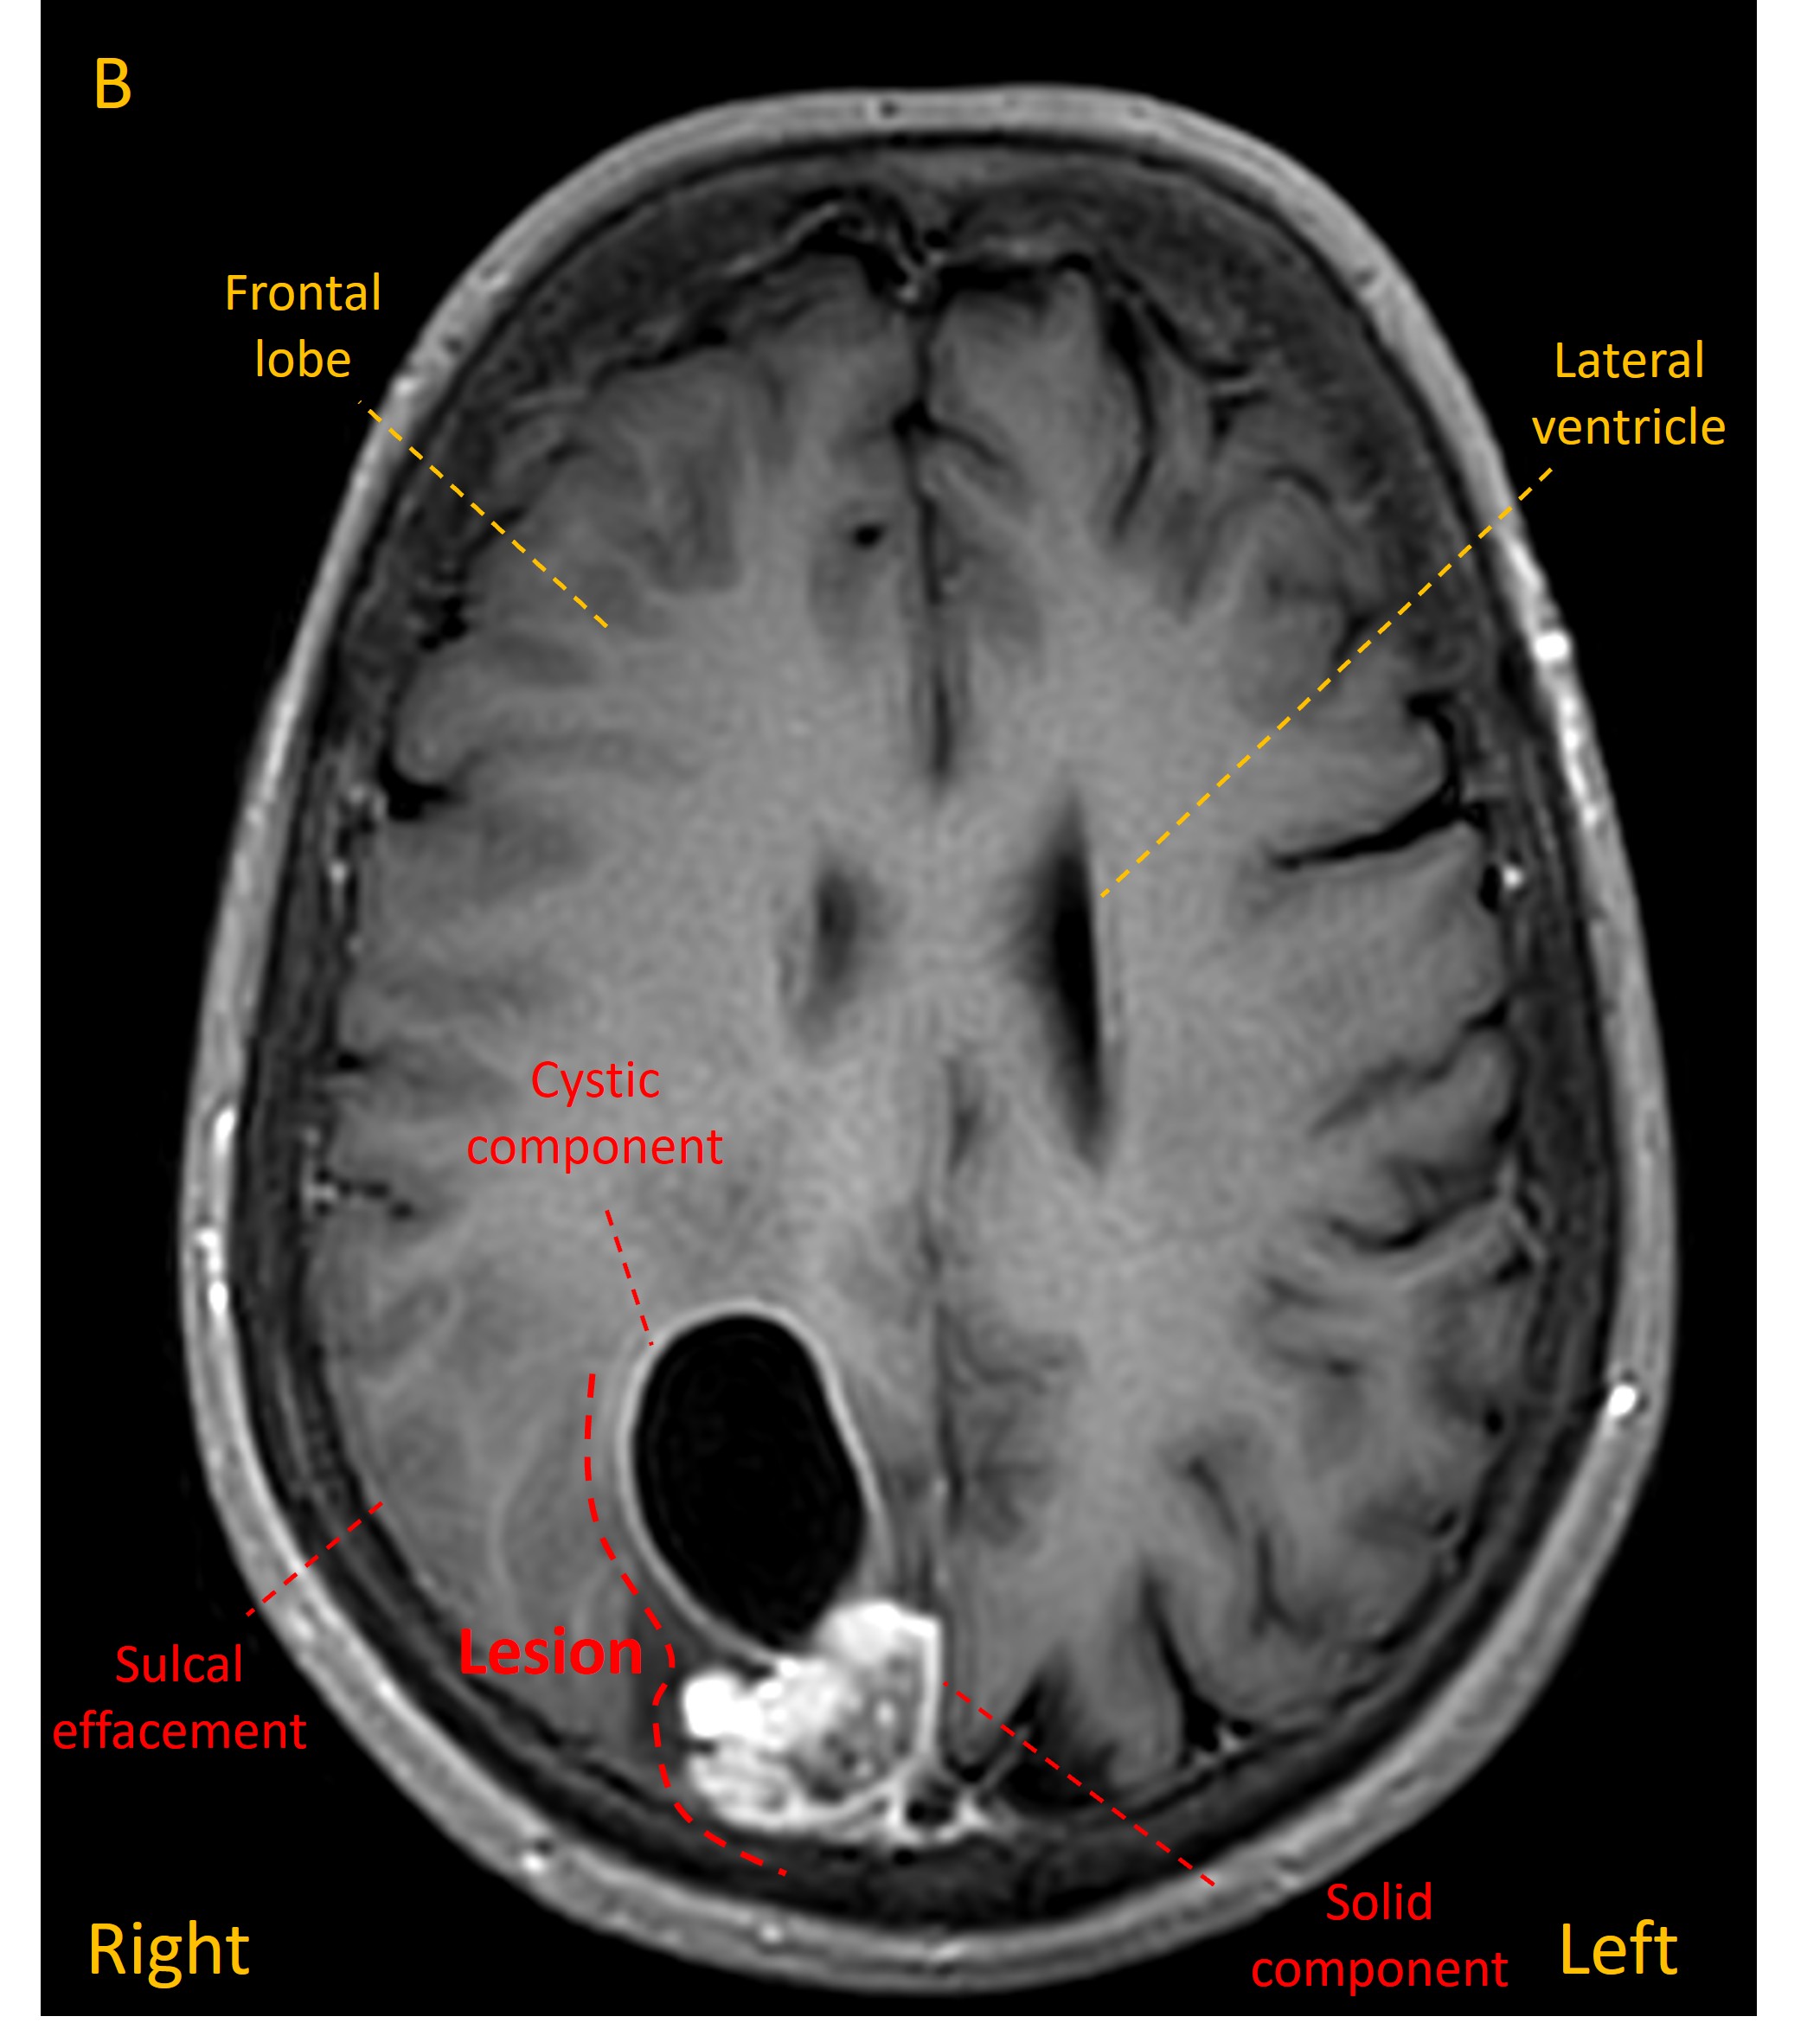

An MRI revealed a mass in the right parietal lobe with a solid component and a deeper cyst, associated with some white matter oedema and some sulcal effacement (images A-C).

MRI 3